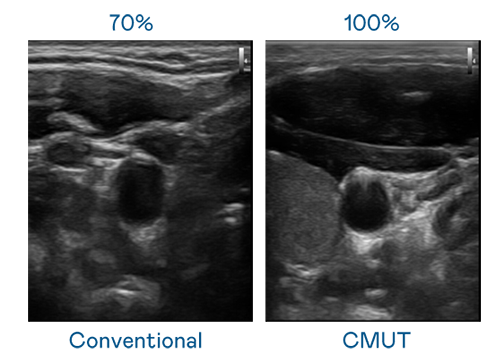

CMUT 技术是一种用电容式微机电元件来产生超音波讯号的技术。与传统 PZT 压电式技术相比,CMUT 频宽增加 30%,更宽频的超音波讯号让影像解析度大幅提升,是实现高影像品质医疗超音波扫描、促进精准医疗发展的关键技术。

大频宽带来超清晰影像

超音波影像的解析度高低,首先取决于探头能发出的讯号频宽。XPJ(中国大陆) CMUT 可提供高清晰的超音波讯号,提供高频宽、高灵敏度、影像纹理细节更高的超音波影像,协助医护人员缩短影像判读时间及利用精准的医疗影像进行诊断。